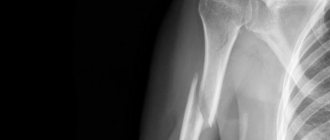

Jaw fracture on x-ray

X-ray data are of key importance in the process of diagnosing a mandibular fracture. Often, several images are taken in different projections (anterior, lateral radiographs).

If a mental fracture of the lower jaw is suspected, a targeted radiograph is taken along with a survey radiography. To determine the integrity of the condylar process, special placements are used (according to Schuller, Parma).

An x-ray of a fracture of the lower jaw reveals a violation of the integrity of the bone in the form of a thin strip of clearing. It is necessary to differentiate a fracture of the lower jaw from other injuries to the bones of the maxillofacial area, as well as from soft tissue bruises.